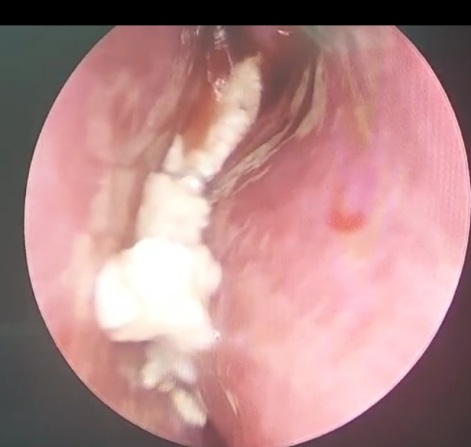

Hình ảnh nấm  xoang bướm